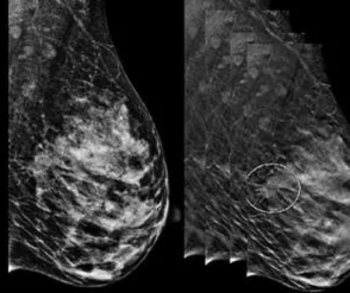

Artificial intelligence (AI) assessment of mammography images may significantly enhance the prediction of invasive breast cancer and ductal carcinoma in situ (DCIS) in women with breast cancer, according to new research presented at the Society for Breast Imaging (SBI) conference.